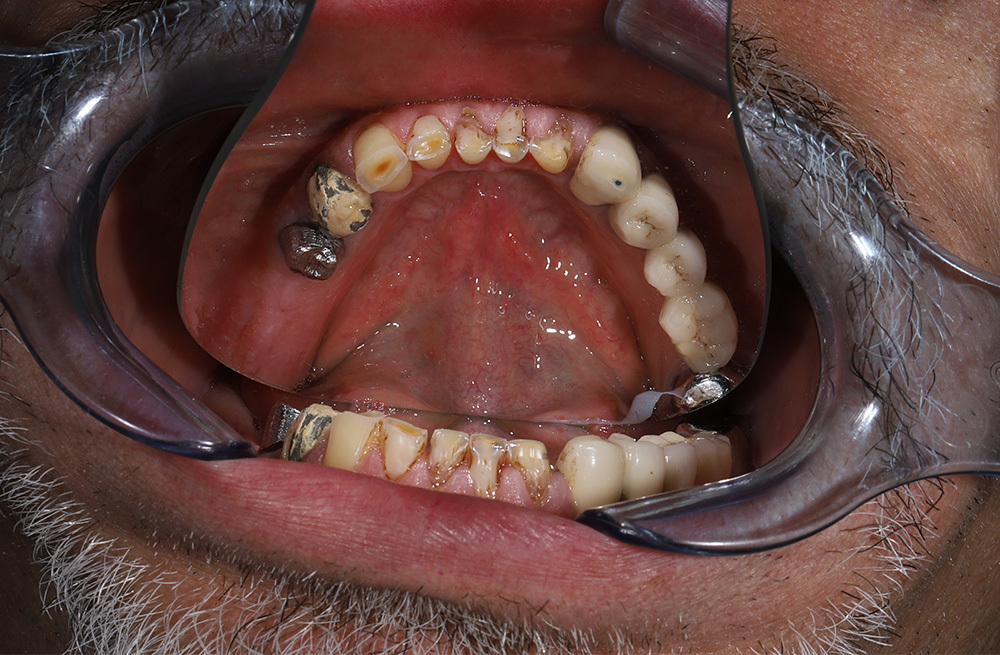

Тотальная реабилитация пациента с ятрогенными поражениями корней по схеме 6 на 6 и надёжной балочной конструкции